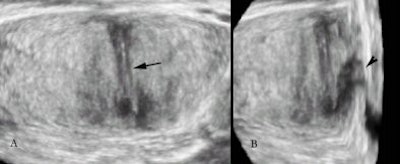

A plane of multiplanar imaging that has been most appreciated is the coronal plane, or what is now known as the C-plane. The exquisite anatomical relationships of the prostate and the seminal vesicles are well brought out by the C-plane. The precise anatomy at the verumontanum can also be appreciated in greater detail.

| C-plane view of the prostate showing the region of the verumontanum (arrow). The proximal urethra (arrowhead) is also seen. |